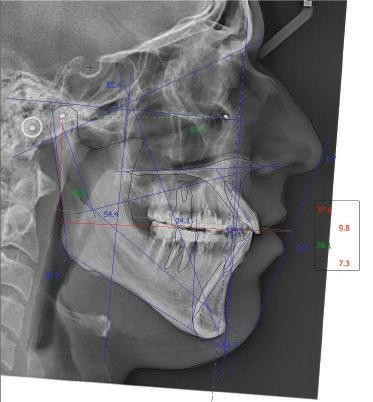

Dental Tribune Bulgarian Edition / октомври 2022 г.16 клиничен случай с алайнери Г орният латерален ре зец е вторият найчесто вродено липсващ зъб.1,2 Поради разполо жението му във видимата зона на усмивката лечение то на подобни случаи нала га мултидисциплинарен под ход, целящ отличен функцио нален и естетичен резултат. Налице са няколко лечебни мо далности, свързани с различ но разпределение на място то: първият вариант е орто донтско отваряне на място и възстановяване на липсва щия зъб с конструкция, под държана от съседните зъби3 или от имплант4, докато при втория подход разстоянията се затварят и премоларът заема мястото на канина.5 Изборът на лечебен подход трябва да бъде направен съв местно от зъболекар и паци ент въз основа на очакванията на последния и предвиди мостта на лечението. Множе ство фактори влияят върху това решение, като напри мер типа малоклузия, размера, формата и цвета на кучеш ките зъби6, оклузалните вза имоотношения (овърджет и овърбайт), лицевия профил, дължината на зъбната дъга и несъответствията в разме ра на зъбите.7 В настоящата публикация се разглежда случаят на жена в зряла възраст с вродена лип са на горен ляв латерален резец. Бяха приложени про зрачни алайнери за отваряне на място за единичен им плант и бяха постигна ти функционална оклузия и отлична естетика. ПРЕДСТАВЯНЕ НА СЛУЧАЯ Диагноза Пациентката бе на 32 годи ни, когато лечението започна, и първоначалното ѝ състоя ние бе следното (фиг. 1–3): липсващ горен ляв латерален резец; клас II, подклас I малоклузия; отклонение на горната сре динна линия вляво; Доклад на клиничен случай ЛЕЧЕНИЕ С АЛАЙНЕРИ НА ПАЦИЕНТ С АГЕНЕЗИЯ НА ЛАТЕРАЛЕН РЕЗЕЦ Д-р Iro Eleftheriadi и д-р Christodoulos Laspos, Гърция и Кипър Фиг. 1a–h Предоперативни лицеви и интраорални снимки. Фиг. 2a–e Дигитални модели преди началото на лечението. Фиг. 3 Панорамна снимка преди лечението. Фиг. 1a Фиг. 1d Фиг. 1f Фиг. 2a Фиг. 2d Фиг. 2b Фиг. 2e Фиг. 3 Фиг. 2c Фиг. 1b Фиг. 1e Фиг. 1g Фиг. 1h Фиг. 1c

Dental Tribune Bulgarian Edition / октомври 2022 г. 17клиничен случай с алайнери леко струпване в долната че люст; несъответствие по Болтън (мандибуларен излишък от 3.06 мм във фронталната зона и общо 1.47 мм); издължено лице с лицева аси метрия; конвексен профил с ретруди рана долна челюст и проми нентен нос. На мястото на зъб #46 бе на лице имплант, а зъби #16 и 26 са ендодонтски лекувани. Тези зъби бяха асимптоматич ни, затова бе взето решение да се прави релечение само при нужда. Мъдреците липсваха. Анализът на телерентгеногра фията (фиг. 4) показа ретрог натна мандибула (SNB: 74.2°) и нормална инклинация на резците както в

Цели на лечението и лечебен план Целите на лечението бяха следните: нивелиране и подреждане на зъбите и в двете зъбни дъги; отваряне на пространство за липсващия латерален резец; коригиране на отношенията при канините и моларите до клас I; и корекция на отклонението на срединната линия. Лечебният план включваше: корекция на отношенията при кучешките зъби и мола рите до клас I с дистализира не на максилата; отваряне на пространство в областта на #22 за поставя не на единичен имплант; корекция на срединната ли ния; и създаване на място за раз ширяване на зъб #12 и апрок симална редукция в долната челюст с цел подобряване на несъответствието по Болтън и осигуряване на подобра оклузия. Изпълнение на лечебния план Този случай бе изпълнен със системата за алайнери Invisalign (Align Technology). Одобреният първоначален лечебен план предвиждаше 49 алайне ра с дистализиране на задни те горни зъби до клас I (прибли зително с около 3.5 мм; фиг. 5). За бъдещия имплант в областта на липсващия латерал бе планирано пространство от 6.5 мм, докато във фронталния сегмент на долната челюст бе предвидена апроксимална редук ция. В дясната страна бутон за ластици клас II бе поставен на зъб #47 вместо на зъб #46, за да не се увреди короната на импланта. Понеже пациентката жи вееше в чужбина,

следните казуси: недобра оклу зия в дисталните зони по вре ме на дистализирането на гор ната челюст и накланяне на зъб #21 (фиг. 7). Последното се дължи на липсата на компози тен атачмънт на този зъб, каквото не бе зададено в пър Фиг. 4 Телерентгенография и цефалометричен анализ преди началото на лечението. Фиг. 5a–e Одобреният първоначален лечебен план. Фиг. 6a–h Снимки по време на лечението, показващи нуждата от внасяне на някои корекции. Фиг. 4 Фиг. 5a Фиг. 5d Фиг. 6a Фиг. 6d Фиг. 6f Фиг. 6b Фиг. 6e Фиг. 6g Фиг. 6h Фиг. 6c Фиг. 5e Фиг. 5b Фиг. 5c

Dental Tribune Bulgarian Edition / октомври 2022 г.18 воначалния план. Тези пробле ми бяха адресирани чрез допъл нителна поръчка на алайнери с торк контрол и зададено екст рудиране на задните зъби с цел установяване на добри оклузал ни контакти в дисталните об ласти, като бяха предвидени и оптимизирани атачмънти с контрол над корените за корекция на ангулацията на макси ларните резци (фиг. 8). Резултати от лечението Панорамната рентгено графия след ортодонтското лечение показа благоприятна паралелна позиция на съседни те зъби, подходяща за поставя не на имплант в областта на #22, както и конвергенция на ко рените на зъби #44 и 45 (фиг. 9), но преценихме, че няма да от деляме допълнително лечебно време за коригирането ѝ поради факта, че пациентката бе мно го доволна от постигнатия до момента резултат. След при ключване на лечението бяха постигнати отлични взаимо отношения клас I при мола рите и канините, а срединни

(LFH: 56.5 mm) и размерите на меките тъка ни останаха непроменени. На клонът на горните резци бе за пазен (Ui–FH: 115.8°), а долните резци бяха леко наклонени ве стибуларно (Li–APog: 30°; фиг. 16). ДИСКУСИЯ Липсата на зародиш на по стоянен горен латерален резец е налице при 3.5–6.5% от евро пеидната раса, като при жени е по-честа, отколкото при мъ жете в съотношение 3:2.8–10 Възможни са няколко лечебни подхода, включително замя ната му с преоформен канин, отваряне на място чрез орто донтско лечение и протетич но възстановяване, както и ав тотрансплантация. Устано вено е, че изборът за затваря не на място или за отваряне то му все още подлежи на дис кусия сред ортодонти и проте зисти.11,12 Според литературните дан ни затварянето на простран ството и замяната на липсва щия латерал с канин се предпо чита в случаи на едностранна липса на зародиш, балансиран профил, кучешки зъби и премола ри със сходна форма и цвят, дву челюстна протрузия или клас II малоклузия.13–15 Отваряне на пространство по-често се изби ра при клас I, наличие на диасте ми и треми в горната зъбна дъга или голяма разлика в размерите на канини и премолари.16 Скорошно проучване е уста новило, че изборът на лечение при конгенитално липсващ ла терал е пряко свързан със след ните фактори17: възрастта на пациента при започване на лечението; индивидуалните особености при всеки конкретен случай; и сътрудничеството между специалистите в лекуващия екип. Макар да има проучвания, фа воритизиращи леченията със затваряне на място11,18, всеки случай трябва да бъде оценяван индивидуално. В презентирания в тази статия случай бе взето решение за отваряне на мяс то и протетично възстановя ване, понеже целта бе да се по стигнат клас I отношения при канините и моларите, както и по-широка усмивка. За да се из бегнат компромиси, след лече нието бе постигнат клас I при моларите и кучешките зъби, несъответствието по Болтън бе подобрено и срединната ли ния бе коригирана. Други изслед вания демонстрират отлични естетични и функционални ре зултати при лечение с отваря не на място и протетична ре хабилитация.19 И двете лечеб ни модалности са подходящи за третиране на вродена лип са на зародиш на латерал и да ват сходни функционални и па родонтални резултати20, като при едно проучване

ти и клас II ластици е устано вено, че осигурява достатъч на дистализация без промяна на лицевата височина.23 Както се видя от цефалометричния анализ, точно това бе постиг нато и в представения случай като се има предвид, че лице вата височина остана същата като първоначалната. Предвид леката тенденция към дистал Фиг. 8a–e Поръчаните допълнителни алайнери. Фиг. 9 Панорамна рентгенография след края на лечението. Фиг. 10a–c Странични (а и с) и фронтална интраорални снимки след края на ортодонтското лечение и поставянето на импланта (b). Зъб #12 все още не беше протезиран. Фиг. 11а и b Оклузални снимки след ортодонтското лечение. Фиг. 7a Фиг. 8a Фиг. 7d Фиг. 8d Фиг. 9 Фиг. 10a Фиг. 10b Фиг. 10c Фиг. 11bФиг. 11a Фиг. 7b Фиг. 8b Фиг. 7e Фиг. 8e Фиг. 7c Фиг. 8c Фиг. 7a–e Интраоралната ситуация по време на лечението. клиничен случай с алайнери

но